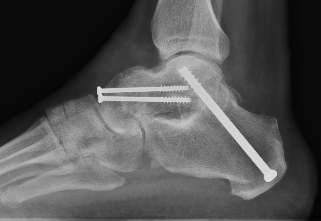

Fixation

- 6.5 mm/ 8.0 mm cannulated screw

- inferior calcaneum into body and neck of talus / talus to calcaneum